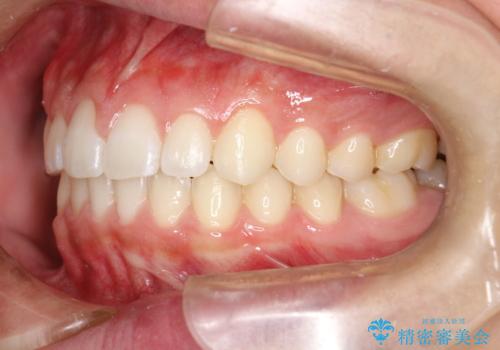

前歯の隙間がきになる インビザラインですきっ歯の治療

- 上の前歯の隙間を主訴に来院されました。

正中に隙間があり、かみ合わせが深い過蓋咬合という状態でした。

インビザラインにて矯正治療を行いました。

しっかり使っていただけたので、スムーズに治療を終了することができました。